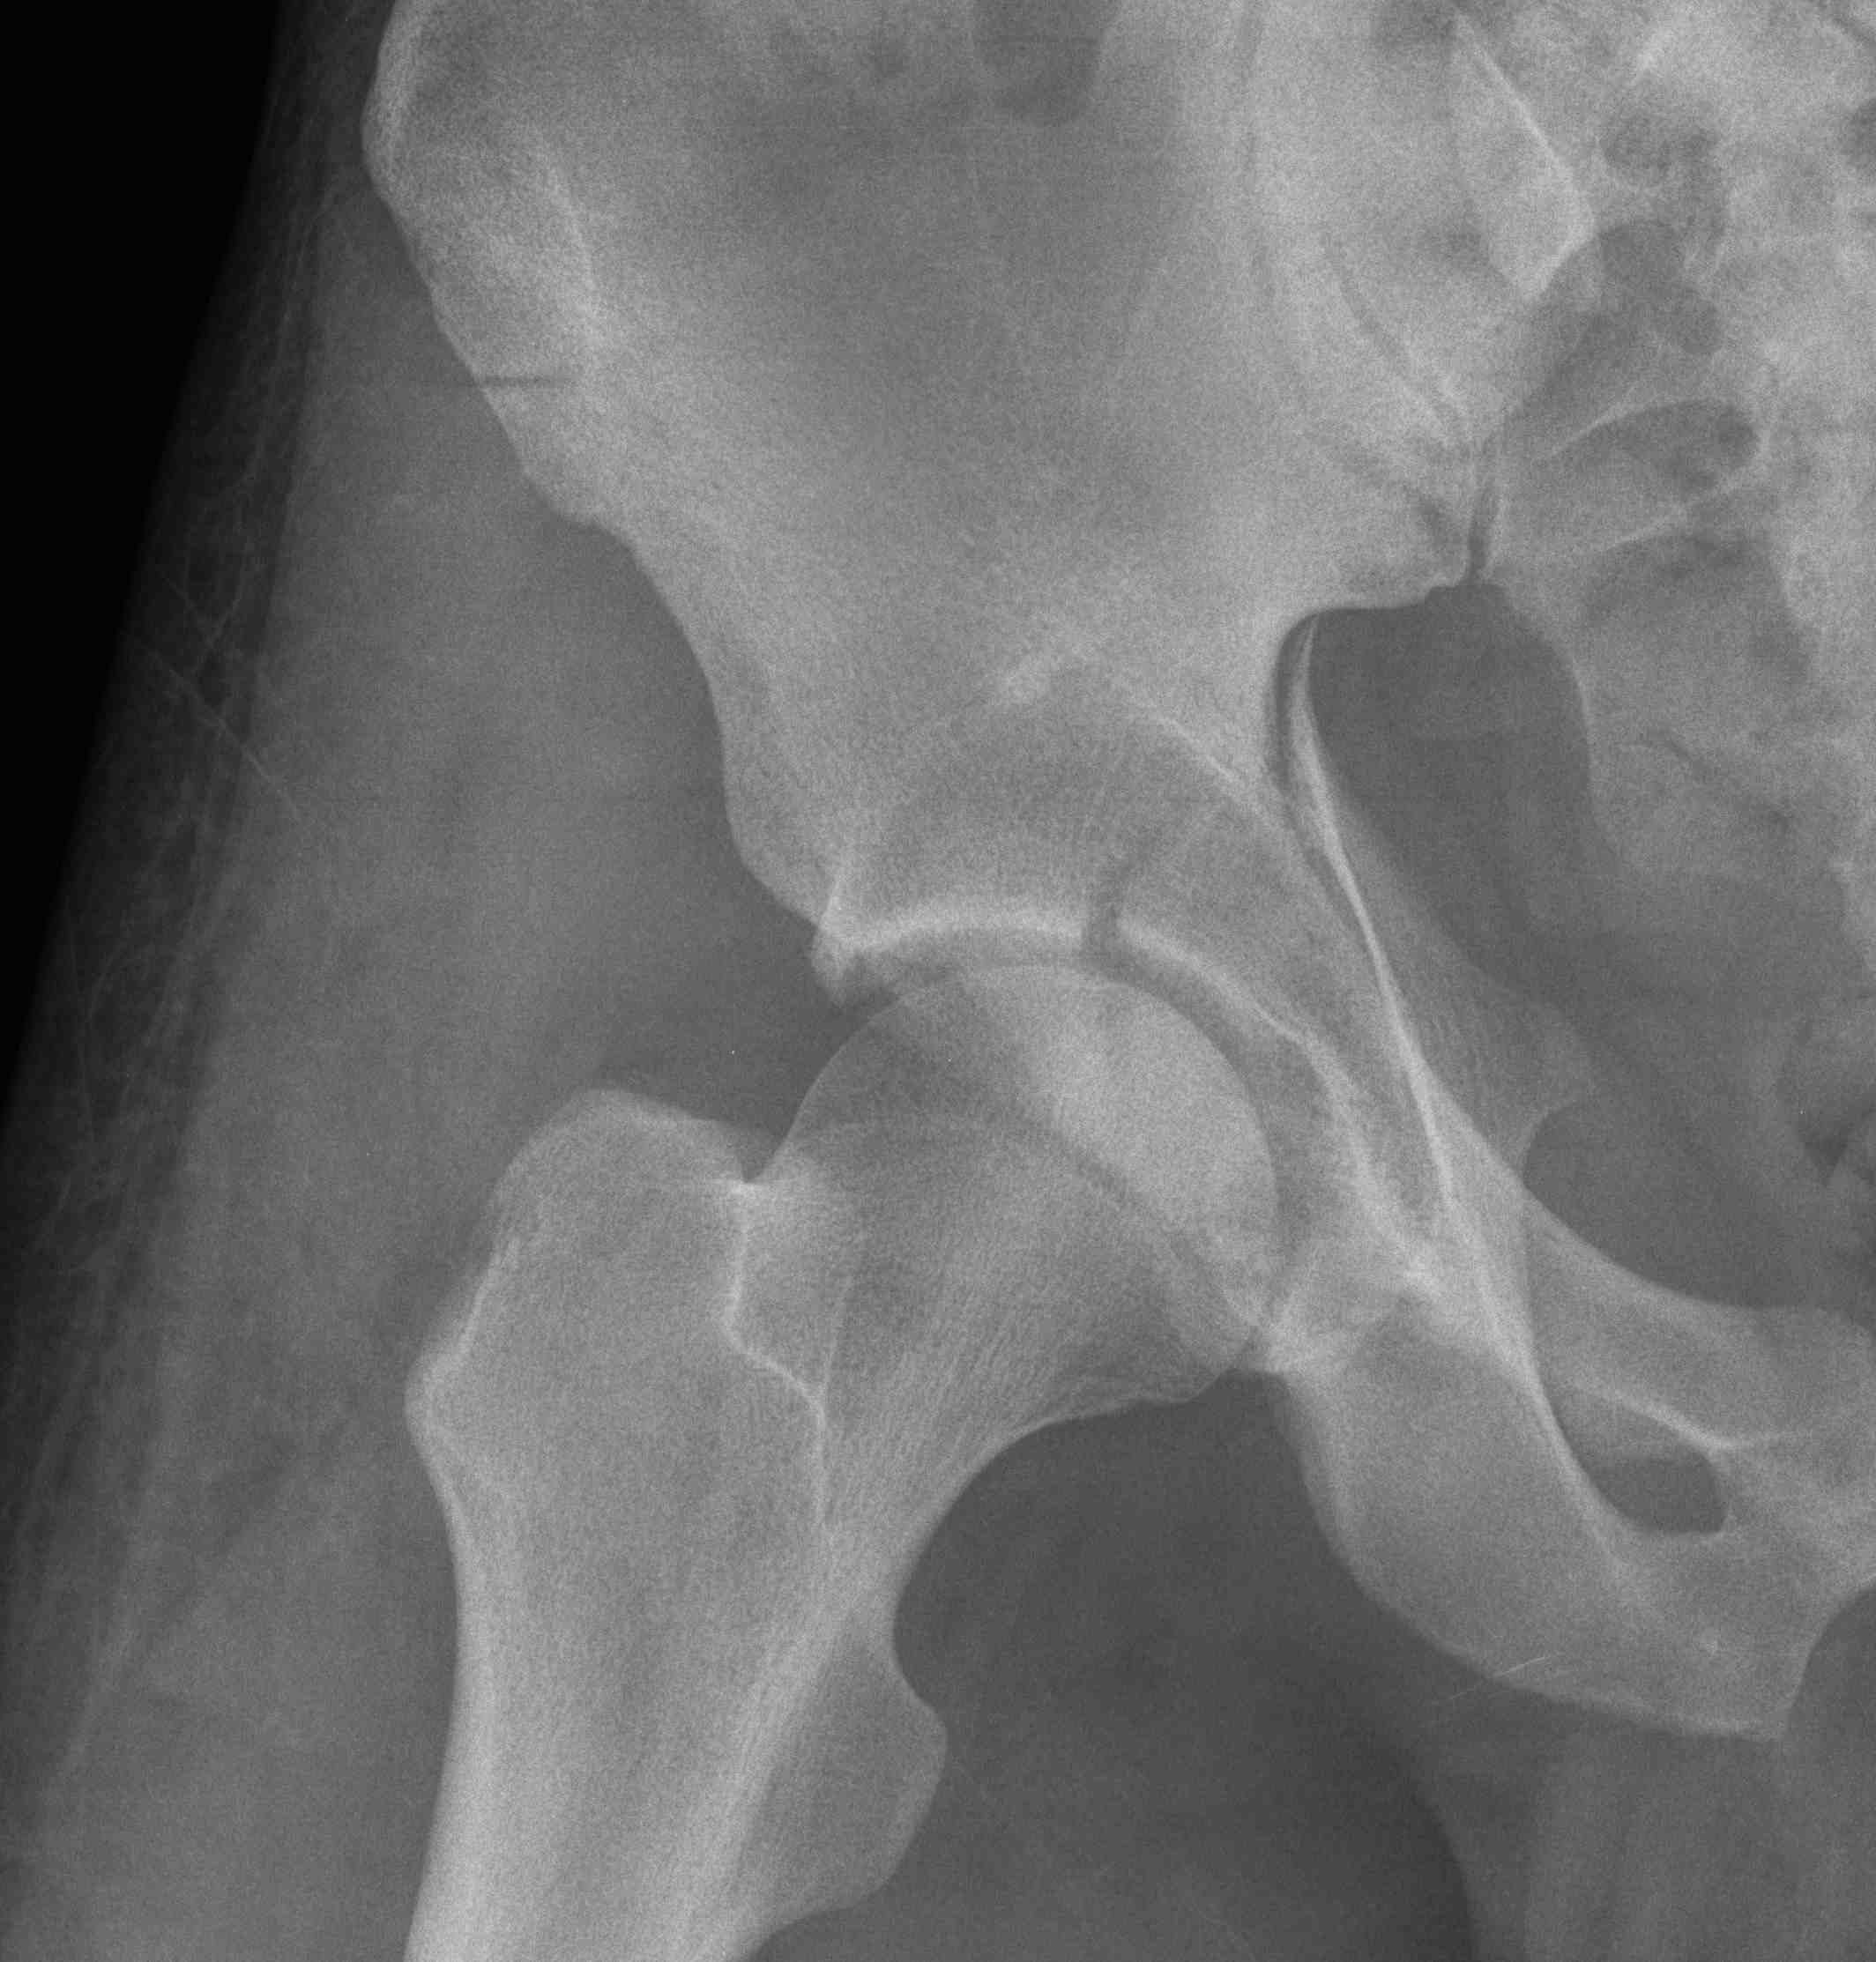

Judet views / 45o obliques

Internal Oblique / Obturator Oblique

- affected side rotated forward

- anterior column + posterior wall

External Oblique / Iliac Oblique

- unaffected side rotated forward

- posterior column + anterior wall